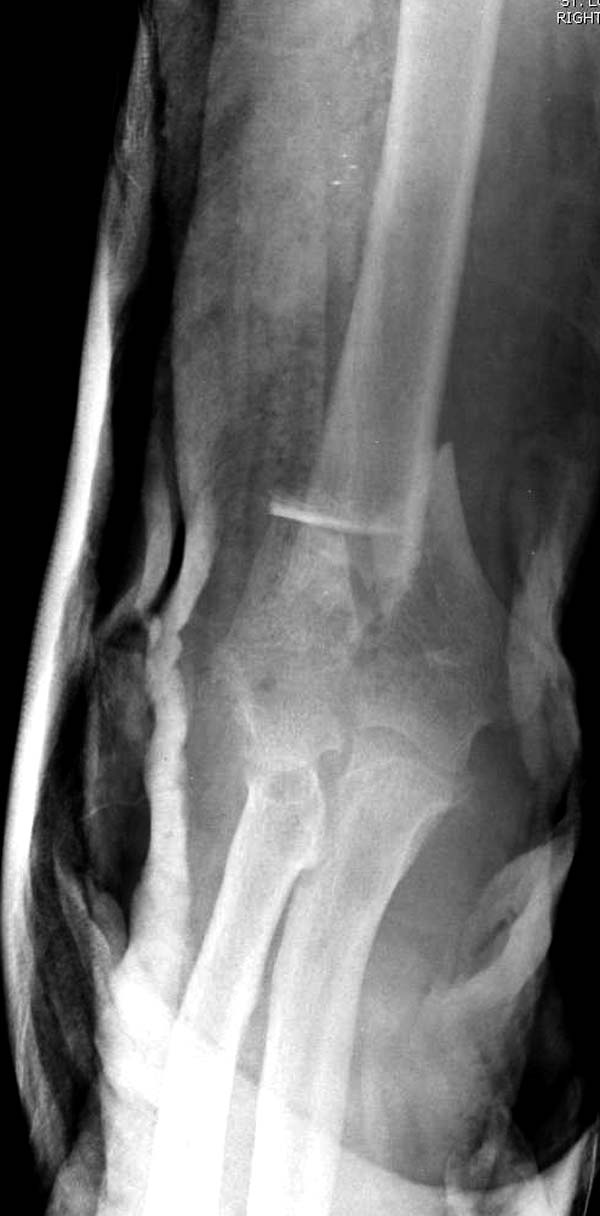

Из представленнего материала видно, что между снимками нет разницы. Отсутствует репозиция не только медиального, а также латерального мыщелка. На боковом снимке мыщелок расположен спереди, а прямом головка луча упирается в край мыщелка, что означает ротацию. Отсутствует компрессия между мыщелками, а один шуруп не смог удержать медиальную сторону, которая при первом же движении рассыпалось.

Ошибка в фиксации привела к дополнительным проблемам, теперь, кроме плеча, надо заниматься с локтевым отростком и невритом. Доступ обычно из двух сторон мышцы трицепса, но некоторым внутрисуставным переломам визуализацию можно создать за счет остеотомии локтевого отростка и как дружно заявили, что фиксацию заканчивает только по Веберу.

В данном случае надо делать ревизию. Среди остальных осложнении ложный сустав локтевого отростка лечить легко, фиксация пластиной и костный графт. Здесь в первую очередь надо создать конгруентость локтевого сустава и вместо толстых шурупов взять тонкие 2.5-3.5 мм. Это как раз случай, когда качество работы зависит не только от опыта хирурга, а и от наличия современного материала по рукой.